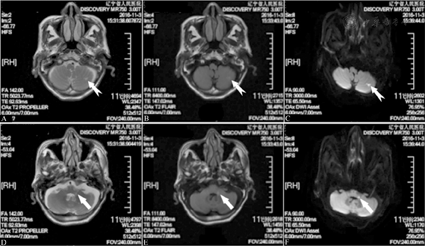

A:磁共振血管造影示右侧椎动脉纤细,双侧大脑后动脉局部走行纤细。B:头颈联合CT血管造影示双侧大脑后动脉P1段局部轻度狭窄;右侧椎动脉纤细,起始部(V1段)可见钙化斑块伴轻度狭窄;右侧颈总动脉起始处、左侧颈总动脉分叉处可见钙化斑块伴轻度狭窄

患者男性,78岁,因"突发行走不稳7 h,加重5 h"就诊。患者于活动中突发站立、行走不稳,表现为向左侧偏斜,迅速加重,同时伴言语不清及恶心、呕吐。就诊时由轮椅推进诊室。发病后无头痛,无视物旋转感,无意识障碍、饮水呛咳及吞咽困难。否认病前外伤史。既往史及个人史:入院前3个月曾因"肢体不自主震颤2 d"住院,口服"美多芭",治疗2个月后症状消失,当时未予明确诊断;否认糖尿病、高血压、冠心病、心律失常等病史。饮酒50余年,3两/d,入院时已戒酒3个月,平素无明确急、慢性酒精中毒表现。否认吸烟史及有毒物质接触史。家族史:否认家族性遗传病、精神病或类似病史。体格检查:生命体征平稳,血压130/75 mmHg(1 mmHg=0.133 kPa),心脏听诊心律齐,各瓣膜区听诊未闻及异常。神经系统检查:意识清楚,言语含糊,语速缓慢似吟诗;双侧瞳孔等大、正圆,直径3.0 mm,直、间接对光反射灵敏;双眼球各方向运动尚充分,无复视,向右侧注视时可见粗大水平震颤;双侧面部痛、触觉对称存在,双侧额部出汗无异常;面部对称,伸舌居正,悬雍垂居中,双侧软腭上抬对称有力;四肢肌力5级,肌张力正常;双侧指鼻试验、跟-膝-胫试验均欠稳准,左侧为重,睁闭眼站立明显摇晃而不能站立,未见不自主运动;四肢痛、触觉正常,关节音叉振动觉、运动觉对称存在;四肢腱反射对称存在,巴彬斯基征阴性。美国国立卫生研究院卒中量表评分3分。认知功能检查正常。辅助检查:血常规示血红蛋白113 g/L;血脂示低密度脂蛋白胆固醇3.29 mmol/L;入院时随机血糖10.05 mmol/L,次日查空腹血糖5.03 mmol/L、糖化血红蛋白6.7%;住院期间3次测量餐后2 h血糖分别为7.56 mmol/L、12.97 mmol/L和10.88 mmol/L;高半胱氨酸15.61 μmol/L;其余血液化验未见异常。心电图和心脏彩超均未见明显异常。颈部血管彩超示右侧椎动脉V2段未探及血流信号,不除外闭塞;左侧颈内动脉起始处(C1段)等回声斑块形成伴中度狭窄(50%~69%)。经颅多普勒超声示双侧椎动脉血流速度减慢。头颅CT示多发性腔隙性脑梗死。头颅MRI示左侧小脑半球点状及延髓背外侧点条状梗死(图1),右侧侧脑室枕角斑片状脱髓鞘改变。磁共振血管造影示右侧椎动脉纤细,双侧大脑后动脉局部走行纤细(图2)。头颈联合CT血管造影示双侧大脑后动脉P1段局限性轻度狭窄;右侧椎动脉纤细(考虑为发育不全),起始部(V1段)可见钙化斑块伴轻度狭窄;右侧颈总动脉起始处、左侧颈总动脉分叉处可见钙化斑块伴轻度狭窄;余颅内外较大动脉形态及走行未见异常,对比剂充盈良好,未见明显充盈缺损(图2)。根据上述头部影像学检查所见,并结合患者突发起病形式,初步诊断:急性脑梗死(左侧小脑半球及延髓背外侧);脑白质脱髓鞘改变;多发颅内外动脉粥样硬化性狭窄及斑块形成;血脂、血糖异常;高同型半胱氨酸血症;轻度贫血。

以往认为Wallenberg综合征是PICA闭塞的结果[22]。近年来对Wallenberg综合征的解剖学、病因及发病机制、临床表现等方面有了许多新的认识,发现PICA闭塞并非导致该综合征的唯一原因。血管造影和病理解剖学研究证实,该综合征更多是因为椎动脉颅内段或起始处狭窄、闭塞以及椎动脉起始处的血栓脱落所致[23,24]。孤立性PICA病变导致的梗死灶相对较小,多位于延髓下段外侧或中下段背外侧[24]。有研究显示,近1/5的椎动脉颅内段近端梗死同时累及延髓外侧(包括ICP)和PICA小脑供血区,同时发生这2种情况通常是由于椎动脉颅内段长节段闭塞,引起PICA和延髓外侧穿动脉血流中断所致[25,26]。穿动脉病变造成的延髓外侧梗死占13%,由于穿动脉比较细小,数字减影血管造影不能显示其走行,仅能根据有无血管危险因素以及梗死灶与供血区特点来推测发病机制[27]。此外,有近20%的延髓外侧梗死患者发病机制尚不明确[28]。本例患者未进行数字减影血管造影检查,磁共振血管造影和CT血管造影均未见梗死同侧PICA或椎动脉颅内段的确切狭窄,其延髓背外侧及小脑腔隙性梗死的责任血管及机制尚不明确,但不排除与椎动脉或PICA发出的分支病变有关,同时也不排除存在后循环血管解剖学变异的可能。椎基底动脉系统变异并不少见,PICA作为椎动脉在颅内最大的分支,其在后颅窝的变异也最多[3,29]。PICA的延髓支为终末支,一般认为供应延髓背外侧[13]。PICA发育变异及供血范围变异被认为是导致延髓背外侧综合征临床表现多样的主要原因[30]。